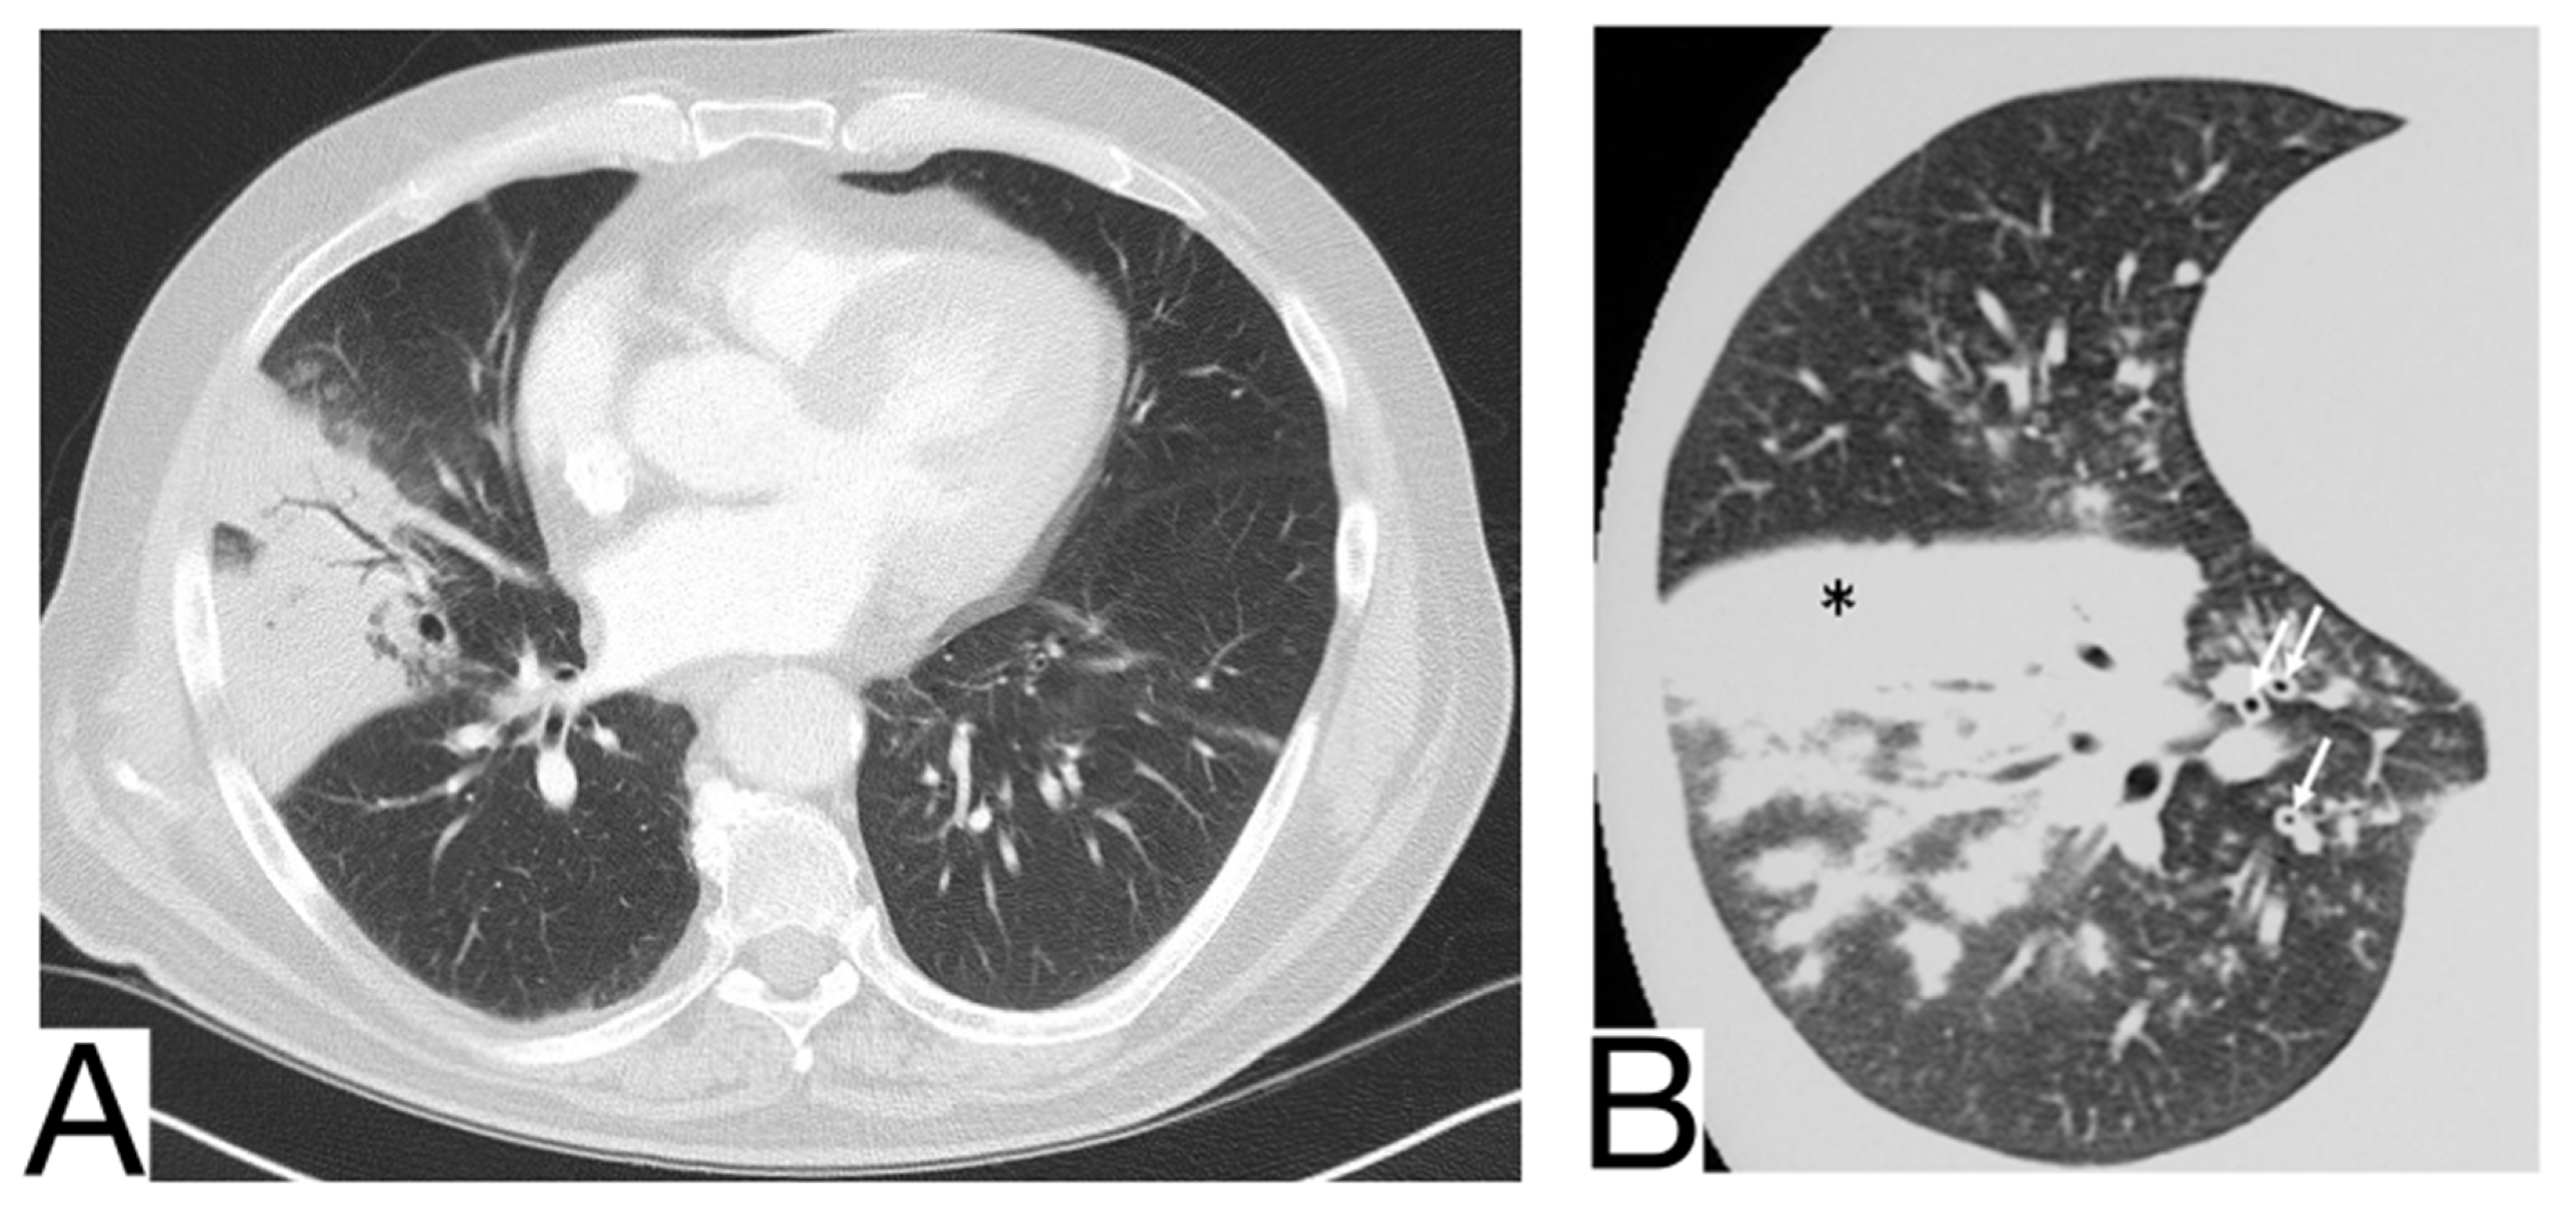

1. Early phase/Stage 1—days 0–4. Ground glass opacities represent the main radiological characteristic [] (Figure 4A);

Figure 4. Imagistic findings in COVID-19 (A). Multiple areas of ground glass infiltration (patient on the third day of symptoms) (B). Bilateral patches of ground glass and subsegmental consolidation (C). Ground glass and consolidation with air bronchogram (8 days after onset) (D). Diffuse ground glass infiltration (white lung appearance). Note. Adapted from Hefeda et al. (2020) [].

2. The progressive phase/Stage 2 refers to days 5–8, and the hallmark is a cobblestone appearance (Figure 4B) coexisting with extensive ground-glass opacities and condensation foci [];

3. Peak phase/Stage 3 is typical for days 9–13, and CT shows pulmonary condensations (Figure 4C), sometimes surrounded by a halo of ground glass.

4. The absorption phase/Stage 4 begins around day 14; areas of ground glass together with linear condensations are appreciable (Figure 4D).

Opacities are usually bilateral and subpleural, having an apicobasal gradient of distribution. Additional radiological features are enlargement of the peripheral pulmonary vessels, while pleural effusions, pulmonary nodules, and mediastinal lymphadenopathy are rare [].